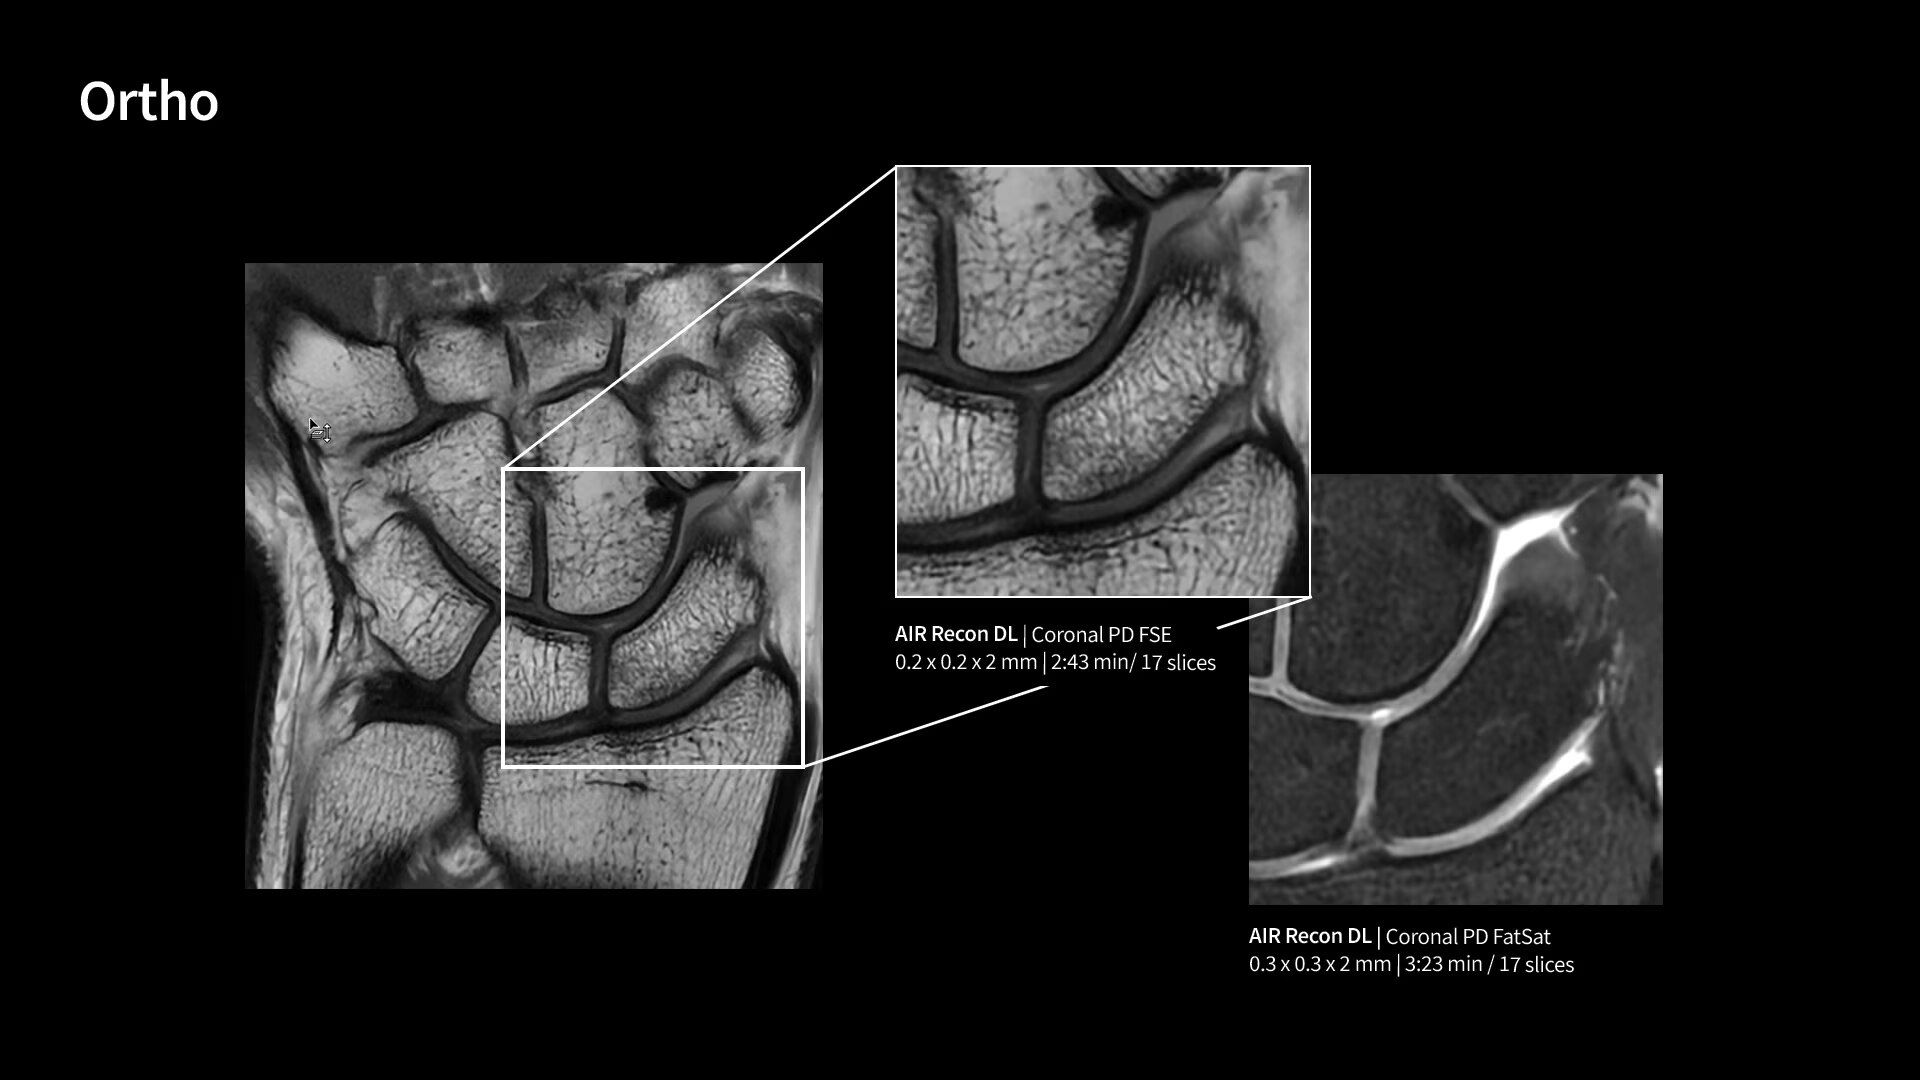

With GE HealthCare's comprehensive suite of deep-learning solutions integrated into SIGNA Sprint, you can unlock the full potential of your MRI system. No need for complicated patient setups or imaging protocols. The exceptional intelligence of our AI solutions offer multiple benefits, with AIR Recon DL giving pin-sharp images, Sonic DL accelerating scans up to 12x, and AIR x enabling automated slice placement. All helping to enhance your department’s workflow efficiency, increase patient throughput, and get the diagnostic clarity you need, faster.¹ Meaning you can spend more time on what truly matters—personalized patient care, enabling optimized treatment plans and treatment response monitoring—ultimately, supporting better clinical outcomes.